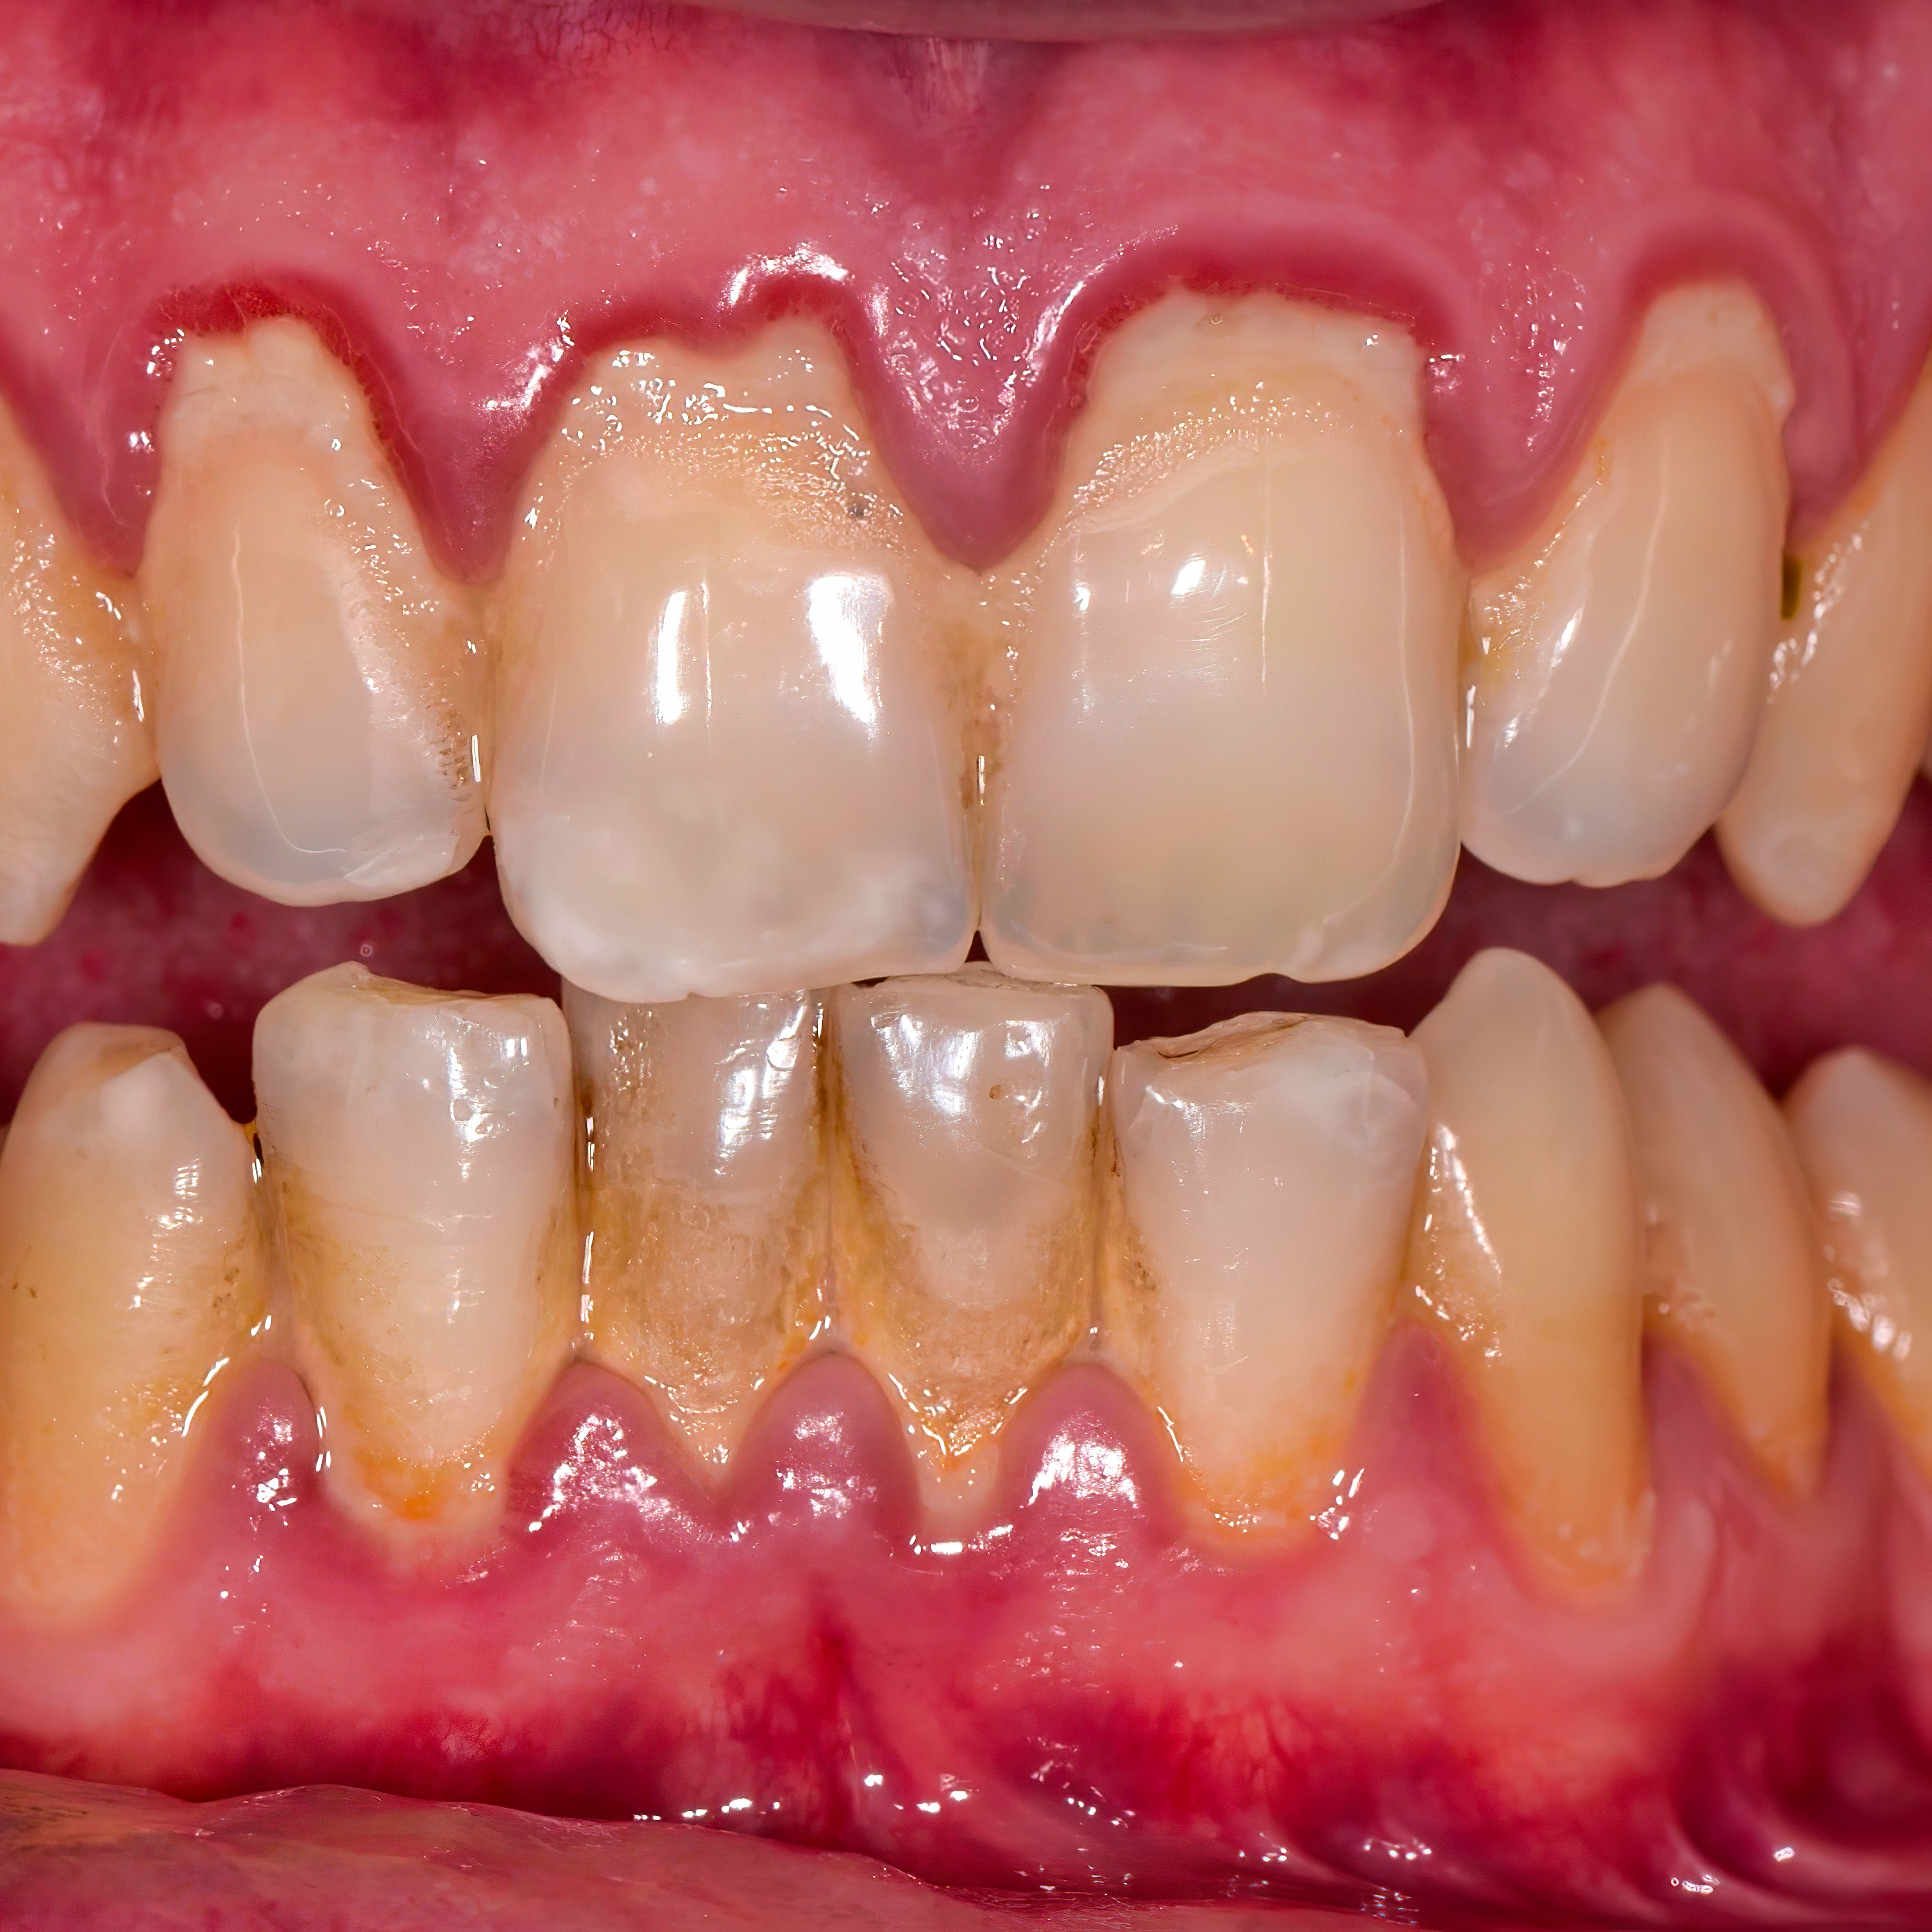

Generalized Periodontal Disease

Generalized periodontitis is a severe form of gum disease that affects multiple teeth and is treated with deep scaling and root planing (see Figure 9). It presents as rapid progression of periodontal tissue destruction, which leads to tooth loss if not treated.

![]() |

Clinical and radiographic example of periodontal disease |

Generalized periodontal disease is caused by a bacterial infection (primarily anaerobic bacteria), hormonal changes (e.g., pregnancy, menopause, genetics), smoking, and diabetes. The patient presents with red, swollen, bleeding, and tender gums. On examination, the patient will have periodontal pockets in excess of 5 mm. The gingiva may bleed, especially when brushing or flossing. The patient may complain of bad breath and loose teeth. A referral to a dentist or dental hygienist is indicated for X-rays and comprehensive dental cleaning.

Antibiotic therapy, as well as scaling and root planing by a hygienist or periodontist, or periodontal surgery by the periodontist, generally is indicated. Lifestyle changes (e.g., smoking cessation, improved oral hygiene, healthier diet, and regular dental check-ups) are necessary to prevent periodontal disease from recurring. If not treated, periodontal disease can lead to tooth and bone loss and an increased risk of heart disease and stroke.2,4,5